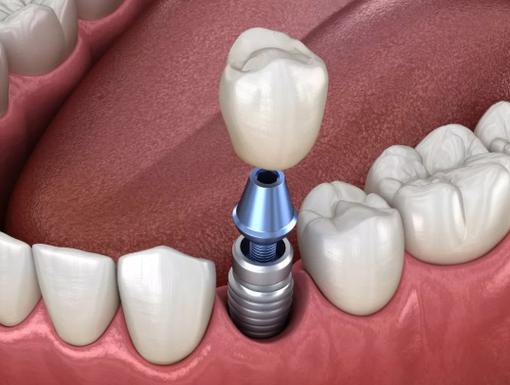

设备与技术:种植牙需依赖先进设备辅助,如CBCT(可三维扫描牙槽骨,精准判断骨量、密度、神经血管位置)、数字化种植导板(实现精准定位,减少创伤)、无菌手术室(避免感染),目前主流技术有微创种植、即刻种植、即刻负重(种牙后当天戴牙)、All-on-4半口/全口种植等,可根据自身需求和经济能力选择。

A:种植牙被称为“人类的第三副牙齿”,若维护得当,种植体可使用20年以上,甚至终身,其优势在于不磨损邻牙( unlike 活动义齿需卡环固定,或固定桥需磨小邻牙),通过种植体独立受力,咀嚼功能接近真牙,且能刺激牙槽骨避免萎缩,但需注意术后保持口腔卫生(每天刷牙、使用牙线、冲牙器),定期复查,避免咬过硬食物(如坚果、螃蟹壳),以延长使用寿命。